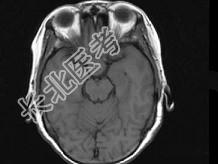

- 单项选择题女,55岁, 1年前出现头痛,头昏, 症状间断性加重,半年后出现视物模糊, 且视力逐步下降,以右侧为甚, 根据所提供图像,最可能的诊断是 ( )

B、颅咽管瘤

C、垂体腺瘤

D、脑膜瘤